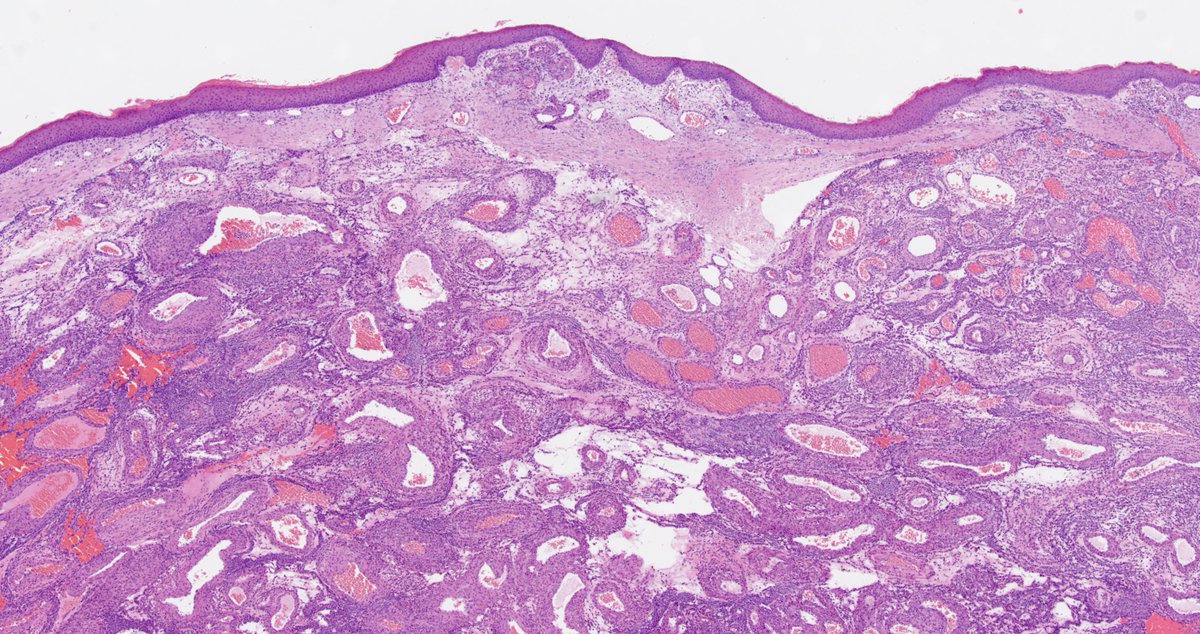

Explants from woman in her mid 40s. Clinical history on req: pulmonary hypertension. IHC is CD1a. Unifying diagnosis?

Thanks to all who engaged! Although uncommon, chronic LCH can lead to severe secondary pulmonary HTN which is what we see here. A spectrum of arterial lesions, including plexiform, dilatation, and medial hypertrophy. Wishing the patient a new lease on life with new lungs!

!